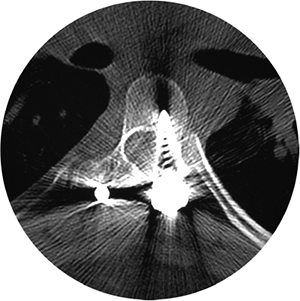

Figure 18.13 A:

This adolescent patient presented with spinal deformity. The standing-position posteroanterior radiograph demonstrates an obvious left thoracolumbar deformity. On careful examination, an abnormality at the lumbosacral junction is suggested. B: A cone-down radiograph of the lumbosacral junction demonstrates a clear hemivertebra. This congenital malformation is the primary deformity, and the thoracolumbar deformity above is a compensatory curve. It is certainly important to recognize this, because treatment of the thoracolumbar curve would lead to marked decompensation to the left.  |